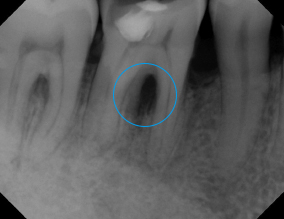

Ozone Treatment :

Bone healing with ozone treatment and SRP

Reverse Gum Disease: Bone Healing